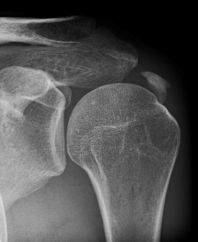

Kalkschulter   Fersensporn

• Kalkablagerungen in der Schulter, die sog. „Kalkschulter“ (Tendinosis calcarea)

• chronische Schmerzen/Entzündungen der Sehnen und Sehnenansätze am Schultergelenk (Tendinosen der Supraspinatussehne/Impingement)

Die Stoßwellen verteilen sich im Körper am besten in liquidhaltigen Bereichen. Erst beim Kontakt der Wellen mit einem festen Körper (z.B. Verkalkung an der Schulter) geben diese Schallwellen ihre hohe Energie an diesen weiter und können dort zu seiner Auflösung beitragen. Der Körper kann den aufgelösten Kalk (man muss sich den Kalk wie nasse und weiche Kreide vorstellen) dann resorbieren und Ihre Schulterschmerzen und die eingeschränkte Beweglichkeit lassen schon nach der 1-2. Behandlung deutlich nach.